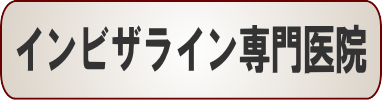

「納得のいくまでカウンセリングをして下さり治療方法も丁寧に説明してくださいました」K.Y様 50歳 女性

子供の矯正が終わったところで幼いころからずっと気になっていた自分の歯の矯正を受けることにしました。

50歳を目前にして不安でいっぱいでしたが、クリニックに行くと納得のいくまでカウンセリングをして下さり、治療方法もひとつひとつ丁寧に説明してくださいました。

全てが心地よく満足しております。

ひとつだけ後悔があるとすればもう少し早くこちらに来ていれば良かったということだけです。

歯並びは第一印象を大きく左右するもののひとつですので、悩んでいる方がいらしたら、ぜひ一日も早くこちらのクリニックにいらっしゃるようおすすめ致します。